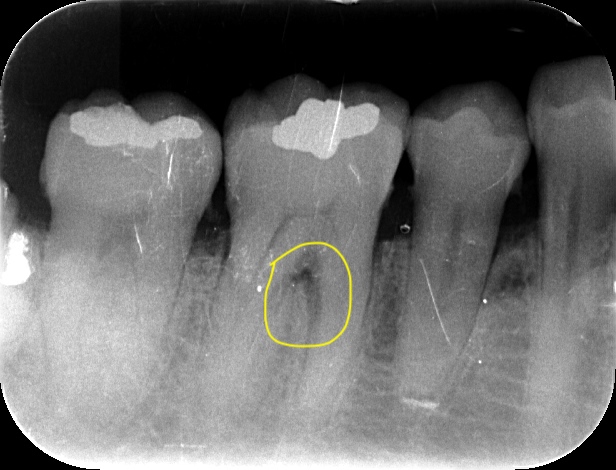

歯周・インプラント治療における再生療法 - クインテッセンス出版。81sSlxbxroL.jpg。リグロスを使った歯周病治療について - 多摩市永山の歯医者「福嶋歯科。裁断済 歯周・インプラント治療における再生療法 リグロスとサイトランスグラニュールを中心に裁断済なので状態が悪いになっています。メルカリ便にて発送致します。。歯周病の再生薬「リグロス」のメリット・デメリット | 高崎市椿町の。お店の情報